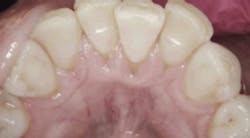

The patient in this case study is like many with gum disease. She has a long history of disease treatment, including regular three-month maintenance visits, yet she struggles to maintain healthy conditions. Bleeding on probing was present at 63% of the sites of her mouth. Thirty-seven percent of her pockets measured 4–6 mm. In addition to initial root debridement and scaling plus regular maintenance, she also had localized antibiotic therapies. The disease persisted.

Periodontal charting on June 8, 2016.